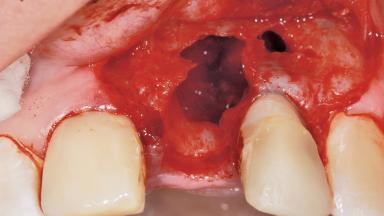

Late Placement of an Implant in a Maxillary Left Central Incisor Site

Bone Augmentation Horizontal|Staged

Bone Volume Deficient horizontally, requiring prior grafting

Augmentation Materials Xenogenous|Membrane